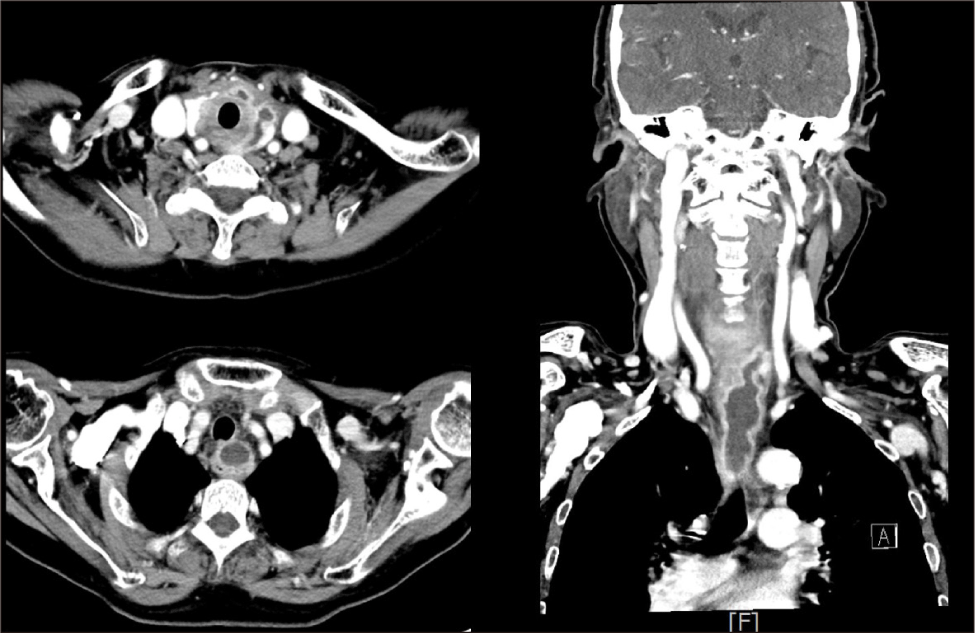

경부전산화단층촬영 결과 갑상선 상극 수준의 후인두벽과 식도 후벽을 따라 저음영 병변이 관찰되었고, 이는 식도 벽 내 농양으로 판단되었으며 내장 공간(visceral space)을 따라 종격동까지 연속적으로 진행하는 양상이었다(Fig. 2).

Fig. 2. Contrast-enhanced CT scan demonstrating an intramural abscess within the esophageal wall. The lesion extends from the level of the upper thyroid pole along the posterior hypopharyngeal and cervical esophageal wall as a localized, well-defined, low-attenuation area with peripheral rim enhancement, indicating pus collection confined within the wall layers and along the visceral space.

영상 진단 측면에서 CT는 식도 벽 비후, 농양강 내 저음영 병변, 주위 연조직의 침윤 소견 등을 통해 병변의 위치와 범위를 평가하고, 병변이 종격동이나 심부 경부로 파급되었는지 확인하는 데 필수적인 역할을 한다.2) 특히 본 증례와 같이 갑상선 상극 수준의 후인두벽과 식도 후벽에 걸쳐 병변이 분포하면서 내장 공간을 따라 종격동으로 연속적으로 확장된 경우, 심부 경부 감염 및 종격동염으로의 진행 위험성을 염두에 두고 병변의 해부학적 범위를 정밀하게 평가하는 것이 중요하다.5,6) 그러나 CT만으로는 점막하 병변과의 감별이 어려운 경우가 많다. 이에 비해 EUS는 병변이 점막하층에 국한되어 있는지 혹은 점막과의 연결성이 존재하는지를 세밀하게 평가할 수 있어 중요한 보조 진단 도구로 자리 잡았다.3,4) 하지만 EUS 유도 FNA는 천공 위험성 때문에 실제 임상에서는 제한적으로 사용된다.